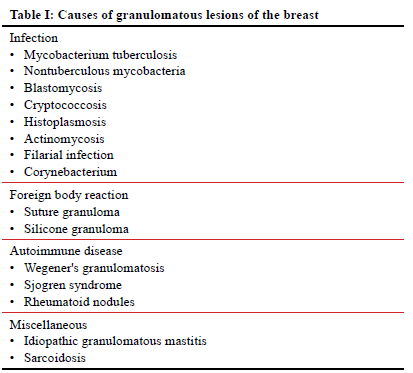

One needs to be mindful that TB is not the only condition that can lead to granulomatous inflammation, as represented in Table I.43 The definitive histological hallmark for diagnosing TB is the presence of necrotising granulomas. However, the absence of necrotising granulomas does not preclude the diagnosis of breast TB, and TB often presents with a combination of necrotising and non-necrotising granulomas influenced by the inflammatory process. Additionally, a small biopsy sample size can result in the non-visualisation of necrotising granulomas.44 Other pathologies, such as infections with non-tuberculous mycobacteria, Wegener's granulomatosis, and granulomatous fungal infections, can also produce necrotising granulomas in breast tissue, as represented in Table II.45 Despite the relatively lower prevalence of granulomatous breast fungal infections compared to breast TB, it is imperative to exclude these conditions, especially in patients with relevant histories, immunodeficiencies, or those residing in endemic regions.45,46 In non-endemic TB areas, the most common causes of granulomatous inflammation of the breast include silicone granuloma, fat necrosis, and idiopathic granulomatous mastitis.46 Tailoring investigative approaches based on patient history, physical exam, and geographical region is crucial, as certain diagnostic tests may be unnecessary in specific contexts. This approach ensures a more efficient and accurate diagnostic process, avoiding redundant or irrelevant investigations. Figure 5 illustrates a proposed diagnostic pathway for breast TB, emphasising the inclusion of serological tests, such as serum ANCA, ACE, and rheumatoid factor, to exclude alternative diagnoses before initiating TB treatment.